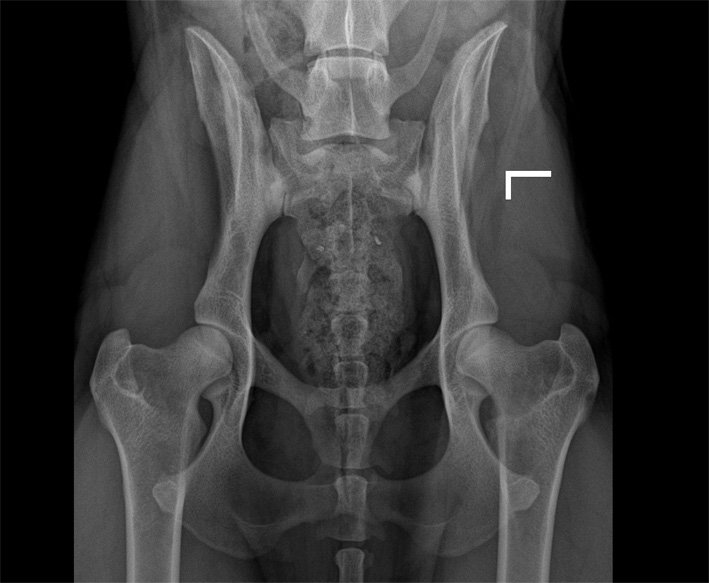

![]() HD-C/ HD-leicht/HD-2 (ab diesem Befund wird im ADRV e.V. kein Hund mehr zur Zucht zugelassen) |

C |

= Grad1 (leicht) |

HD-2 |

leicht |

Leichte Inkongruenz, divergierender Gelenkspalt, NORBERG-Winkel um 100 Grad |